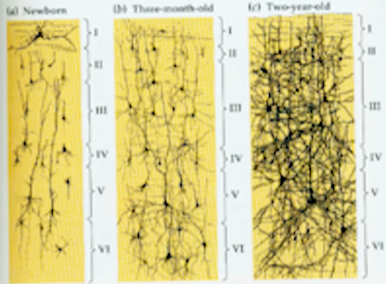

- 学习是神经回路的改变和强化

图3-1 - 智慧是神经连接的密度和它连接的方式

图3-2 - 方式由基因决定

- 密度是后天经验决定